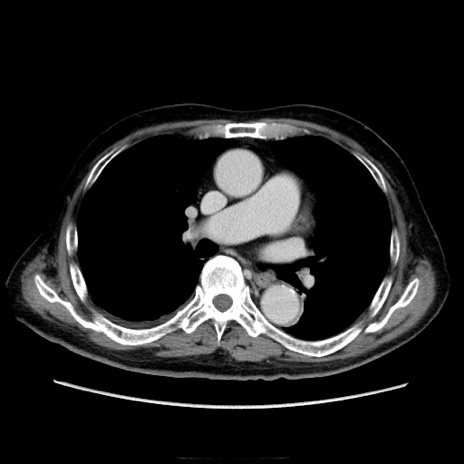

症例21(横断像)

【症例】70歳代男性

【主訴】腹痛

【現病歴】肝硬変・肝細胞癌にてかかりつけの方。約9時間前に食後より腹痛出現。症状が徐々に増悪し、嘔吐出現したため来院。

【既往歴】肝硬変、肝細胞癌(RFA、TACE後)

【身体所見】意識清明、表情苦悶様、BT 36℃、BP 129/78mmHg、P 88bpm、SpO2 97%(RA)、右上腹部から心窩部にかけて圧痛あり、反跳痛なし、筋性防御あり。

【データ】WBC 5800、CRP 0.16